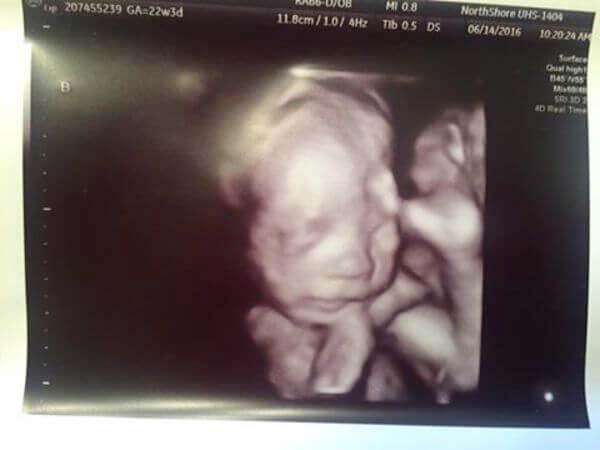

Hon gick till doktorn för att ta ett nytt ultraljud av hennes mage, för att se om allt var bra med barnet. Det var inte bara en bebis i magen utan läkaren kunde berätta för henne vad ultraljudet visade. I Courtneys sköte fanns två pojkar och en flicka som snart skulle födas.

Hon var så lycklig trots saknaden och sorgen, att hon levde i en orealistisk balans mellan kärlek och sorg. Men det var inte slutet på hennes upplevelser, för 25 veckor in i denna graviditet fick hon ännu ett chockerande besked från läkaren.